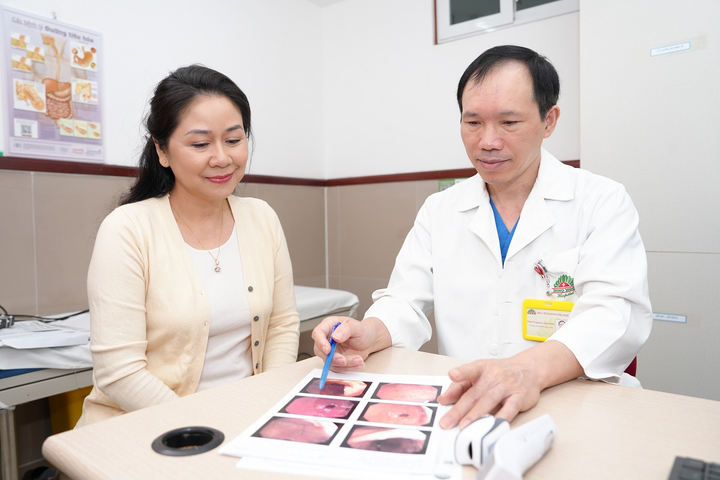

Thăm khám và tư vấn Phẫu thuật thoát vị đĩa đệm với Chuyên gia hàng đầu Việt Nam

Tại chương trình ưu đãi lần này, khách hàng được trực tiếp PGS.TS.BS Hà Kim Trung khám và tư vấn Phẫu thuật thoát vị đĩa đệm (cột sống cổ, lưng, ngực). PGS.TS.BS Hà Kim Trung - Bệnh viện Đa khoa Hồng Ngọc là chuyên gia đầu ngành về Phẫu thuật Thần kinh - Cột sống với hơn 30 năm kinh nghiệm, từng tu nghiệp tại Pháp, Nhật, Úc, đã và đang giữ nhiều chức vụ quan trọng như:

Chương trình khám và tư vấn phẫu thuật thoát vị đĩa đệm với PGS.TS.BS Hà Kim Trung chỉ áp dụng cho khách hàng đặt lịch trướcLà chuyên gia hàng đầu Việt Nam, PGS.TS.BS Hà Kim Trung đã điều trị thành công hàng ngàn ca bệnh khó, lấy lại tầm vận động cho các bệnh nhận thoát vị đĩa đệm: